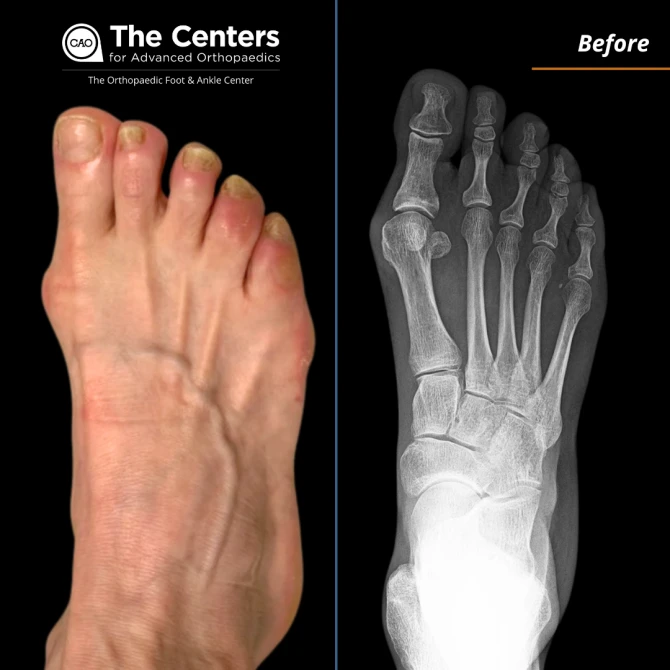

My initial medical issue was a bunion and hammertoe deformity in my right foot. It was causing me a lot of pain and discomfort, especially when I walked.

I had minimally invasive bunion surgery and hammertoe correction on my right foot. I also went to physical therapy here. I could've done PT near home, but I wanted foot and ankle specialists.

I feel great! There's no more pain in my right foot like there used to be. Occasionally, I might have some aches, but I attribute that to getting older. The swelling I initially had has gone down, and my foot looks a lot better now. I'm a school teacher, so I walk about 7 miles a day, and I can do that without any issues now.

Before and After 4 Months Post-Op